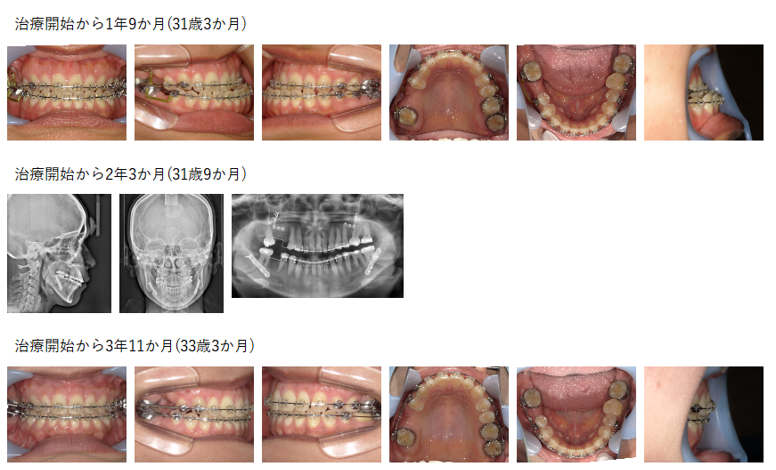

【治療例】初診時年齢:24歳2か月 / 性別:男性 / 主訴:顎のズレ、嚙み合わせのズレ、下の歯が出ている

主訴: 顎のズレ、嚙み合わせのズレ、下の歯が出ている

診断名: 下顎骨の左方偏位を伴ったため左側の交叉咬合を認められた骨格性下顎前突症例

使用した主な装置: マルチブラケット装置、顎間ゴム

抜歯/非抜歯および抜歯部位: 非抜歯

治療期間:4年9か月(2023年2月~は保定期間)

治療回数:41回